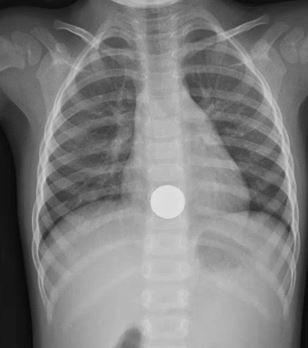

What’s the Diagnosis? Gepost op 20 mei 202020 mei 2020 door netwerkvsseh What’s the Diagnosis? @emdaily.cooperhealth.org Dit delen: Delen op X (Opent in een nieuw venster) X Share op Facebook (Opent in een nieuw venster) Facebook Delen op LinkedIn (Opent in een nieuw venster) LinkedIn E-mail een link naar een vriend (Opent in een nieuw venster) E-mail Afdrukken (Opent in een nieuw venster) Print Vind-ik-leuk Aan het laden... Gerelateerd